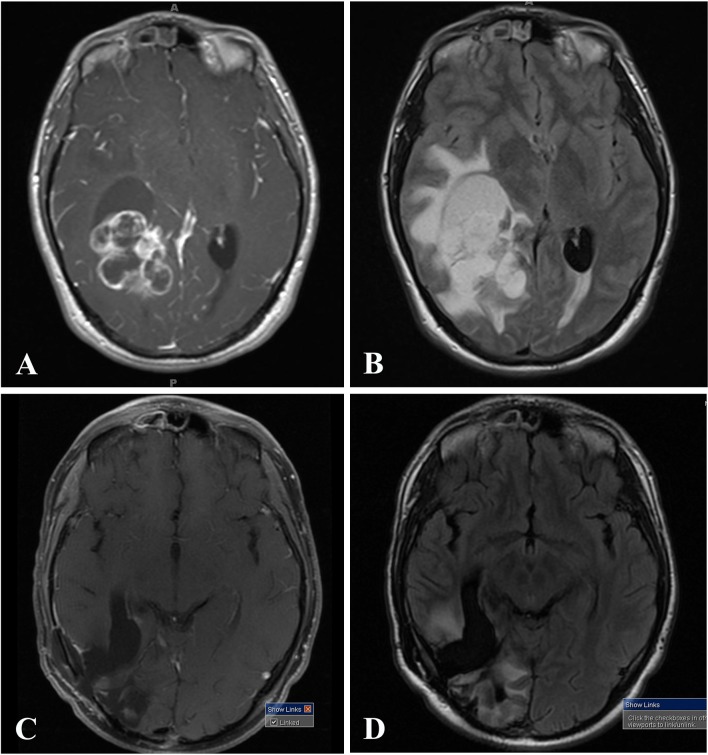

A 19-year-old man developed blurry vision with new headaches in November 2014. He had bilateral papilledema. A MRI brain showed a large right-sided lesion involving the parieto-temporal lobes, hyperintense on T1 and T2-weighted sequences, with significant surrounding vasogenic edema on T2-weighted fluid-attenuated inversion recovery (FLAIR), contrast enhancement post-gadolinium, and a right-to-left midline shift (Fig. 1a, b). The overall appearance of this lesion looked a bit unusual for a classical GBM. He had a subtotal resection on January 30th, 2015, and was diagnosed by a local pathologist with a “GBM”. He completed 6 weeks of radiation therapy (RT) and temozolomide (TMZ). Four months later, a follow-up MRI showed an increase in the size of the enhancing tumor and, despite the possibility of pseudoprogression, a second surgical resection was performed on June 2nd, 2015 and showed “GBM”. Maintenance TMZ was started and follow-up imaging showed stable disease (Fig. 1).

Fig. 1.

MRI of the brain demonstrating a right-sided, large parieto-temporo-occipital mass, which appeared unusual for a classical GBM, with surrounding vasogenic edema and a right-to-left midline shift. a, b Initial MRI of the brain prior to surgery for tumor resection in January 2015. a T1-weighted post-contrast demonstrating heterogeneous enhancement. b T2-weighted fluid-attenuated inversion recovery (FLAIR) shows significant surrounding vasogenic edema. c, d Status-post resection and two cycles of maintenance TMZ in September 2015. c T1-weighted post-contrast. d Status-post resection, T2-weighted FLAIR sequence